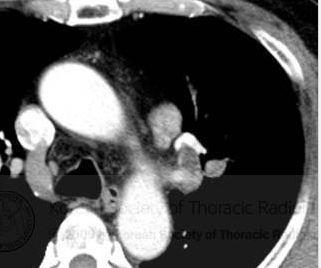

ct显示左肺上叶有支气管内肿块,伴有远端黏液嵌塞,主动脉旁和左支气管